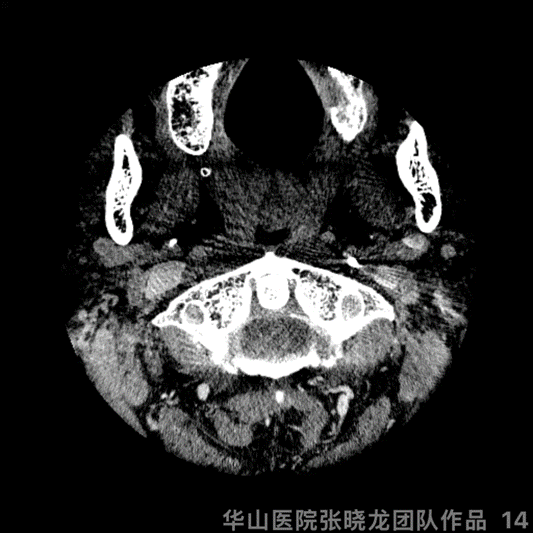

Figure 2. DSA showed the right ACA A1 segment was undeveloped and the right ICA clinoid segment mild/moderate stenosis.

图 2. 脑血管造影示右侧大脑前动脉A1段发育不佳,右侧颈内动脉床突段轻中度狭窄。